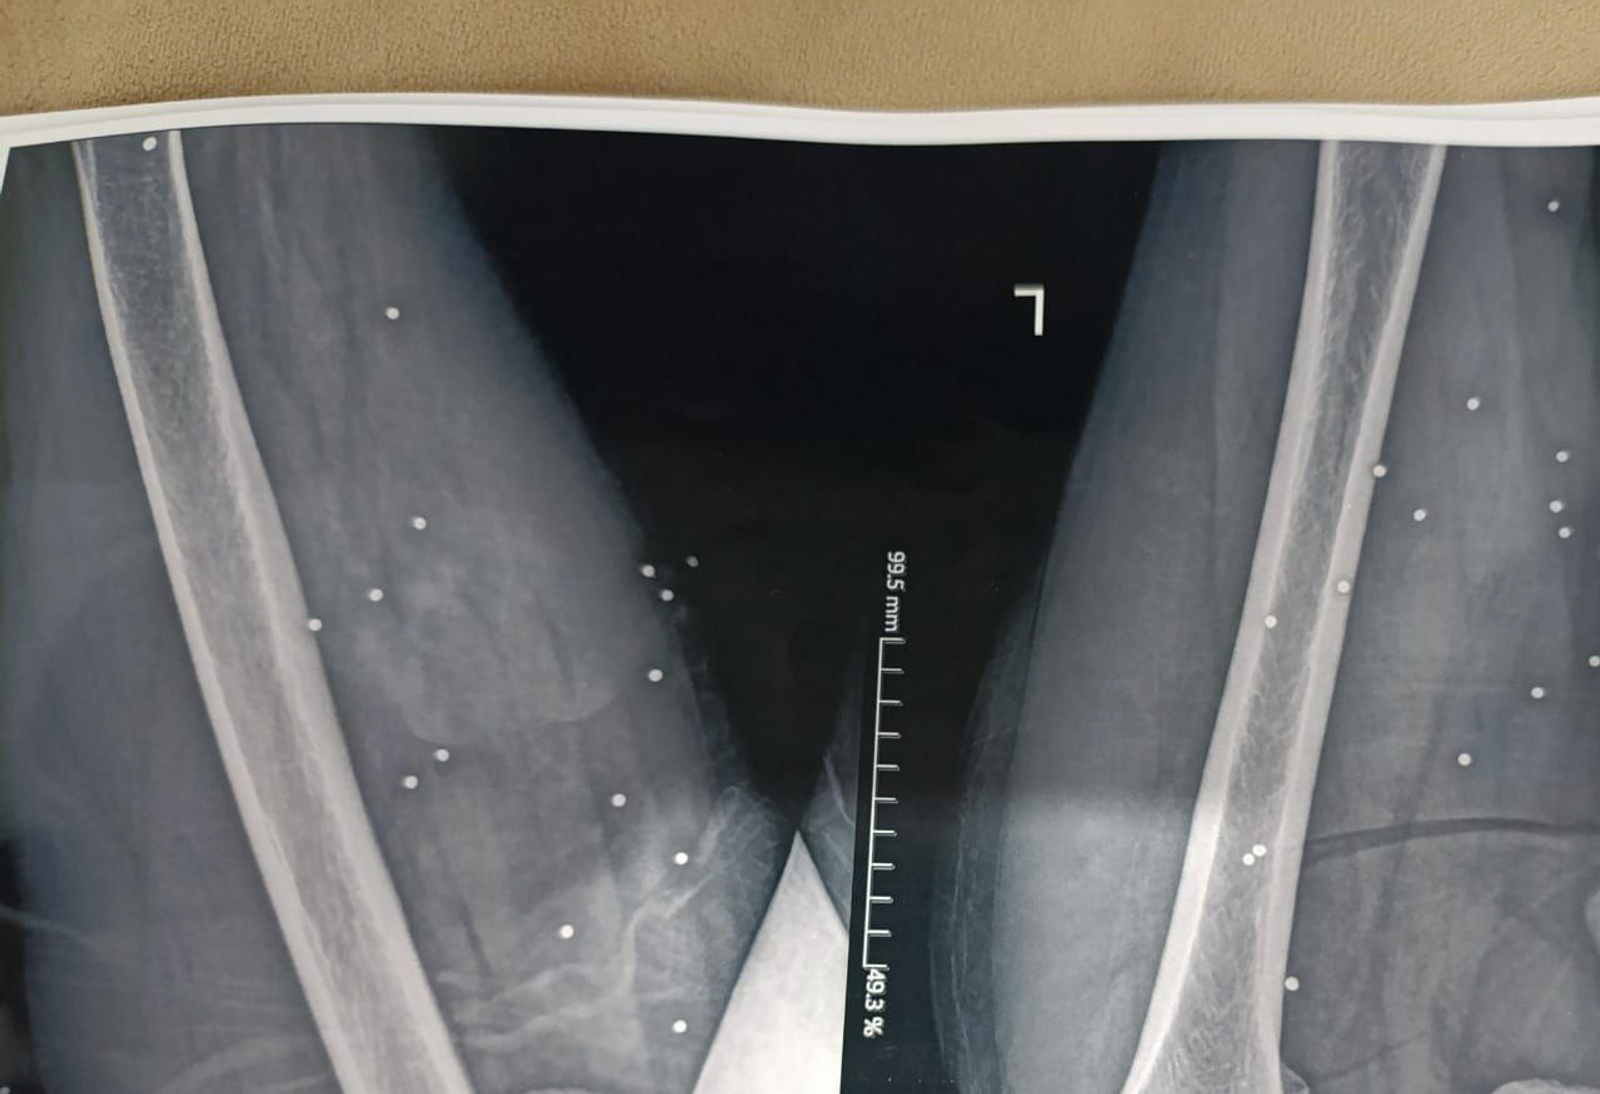

در پرونده «علی»، بیش از ۱۷۴ ساچمه در قفسه سینه راست دیده میشود. تراکمی که نشان میدهد شلیک از فاصله بسیار نزدیک انجام شده است. ریه راست او آسیب شدید دیده و تجمع خون و هوا در اطراف آن مشاهده میشود.

کارشناسان پزشکی گفتهاند حتی با مداخله فوری، خطر مرگ در چنین شرایطی بالاست.

در ۹ بیمار، گلولههای کالیبر بالا همچنان در بدن باقی مانده و در تصاویر دیده میشوند.

در موارد دیگر، مسیر شکستگی استخوان و قطعات فلزی باقیمانده نشان میدهد احتمالا اصابت گلولههای پرسرعت، عامل جراحت بودهاند.

کارشناسان این مهمات را از نوع «تمامفلزی» معرفی کردهاند؛ گلولههایی که معمولا با سلاحهایی مانند ایکی-۴۷ (AK-47) شلیک میشوند و شکل خود را حفظ میکنند.